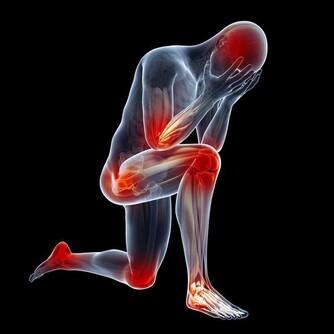

現代社會,很多上班族和學生一天中都要坐上8個小時以上,一些程序員和媒體人甚至會坐上一整天。相關部門表明,每天坐了8~12小時就屬於久坐。長時間坐著不動會給人體健康帶來很大的傷害。

久坐有哪些風險?

經常久坐的人,患上頸椎病的概率會更高。因為人體的骨連接需要足夠的黏液,來保證關節的正常使用。而久坐的人產生的黏液較少,會使骨關節變得乾燥,久而久之會引發頸椎病和關節炎。

此外,長時間保持一個姿勢不動,還會對頸椎動脈供血造成影響,並破壞人體正常生理彎曲,導致駝背和骨質增生。

數據顯示,如果每天久坐超過3個小時,那麼就會減慢人體靜脈血液的流速,容易形成血栓,增加罹患心腦血管疾病的機率,誘發冠心病。久坐還會阻礙大腦的正常供血,長期下來易出現失眠、嗜睡、記憶力下降等情況,甚至引起老年癡呆症。

另外,對於本身患有動脈硬化的中老年人來說,還會加大腦血栓和心肌梗塞發生的風險。